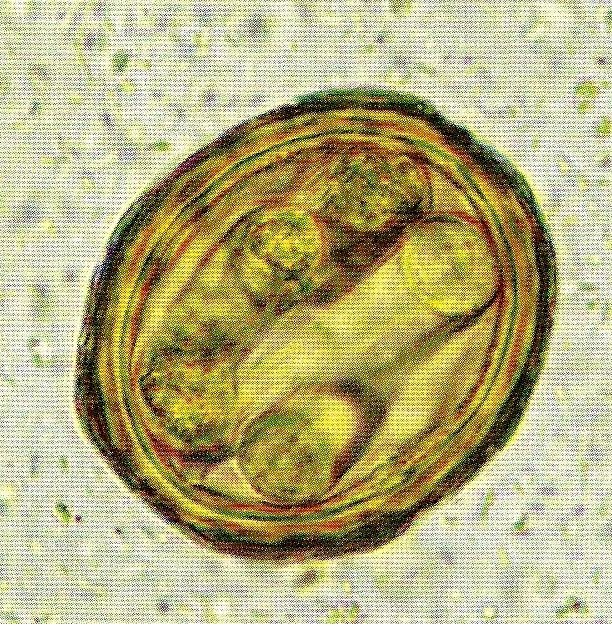

Личинка в яйце аскариды

Личинка в яйце аскариды 107 фотографий